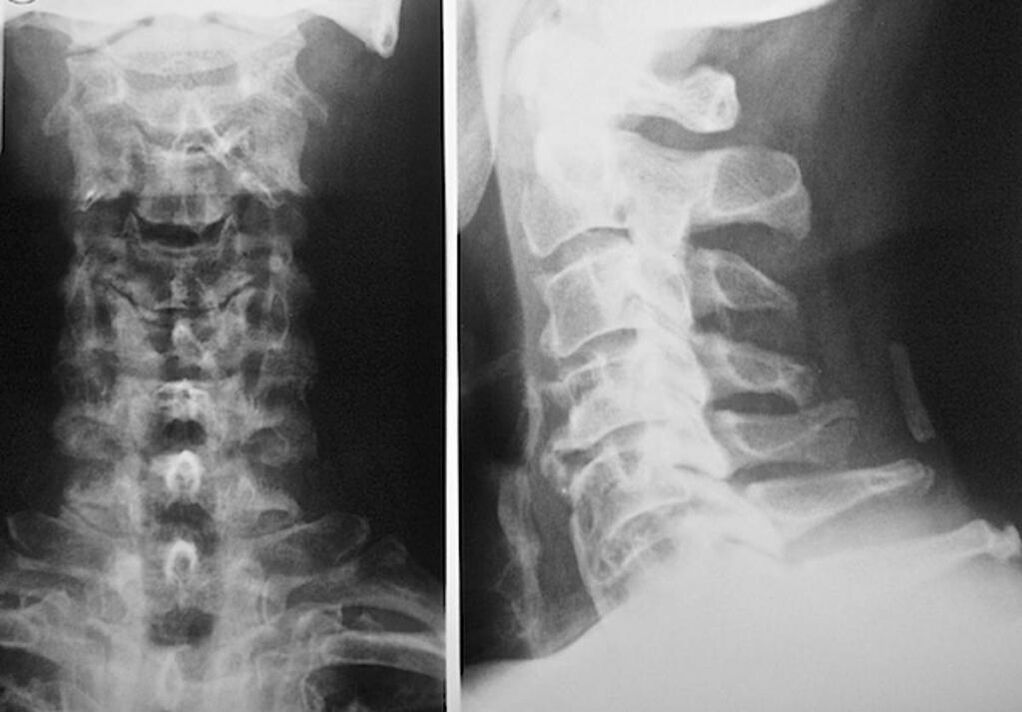

Per la diagnosi e la valutazione accurata delle condizioni dei dischi intervertebrali, vengono utilizzati i seguenti metodi di ricerca:

- Radiografia.

- TAC.

- Tomografia magnetica.

- Scansione a ultrasuoni dei vasi del collo.

Ognuno di loro è completamente sicuro per la salute e non comporta alcuna minaccia di esposizione eccessiva. La diagnosi di osteocondrosi delle vertebre cervicali, il cui trattamento sarà effettuato per il resto della vita, può essere effettuata dopo un semplice esame visivo. Qualsiasi ortopedico può farlo facilmente. Un'eccezione è il primo stadio della malattia, quando non si notano patologie visibili della regione cervicale.